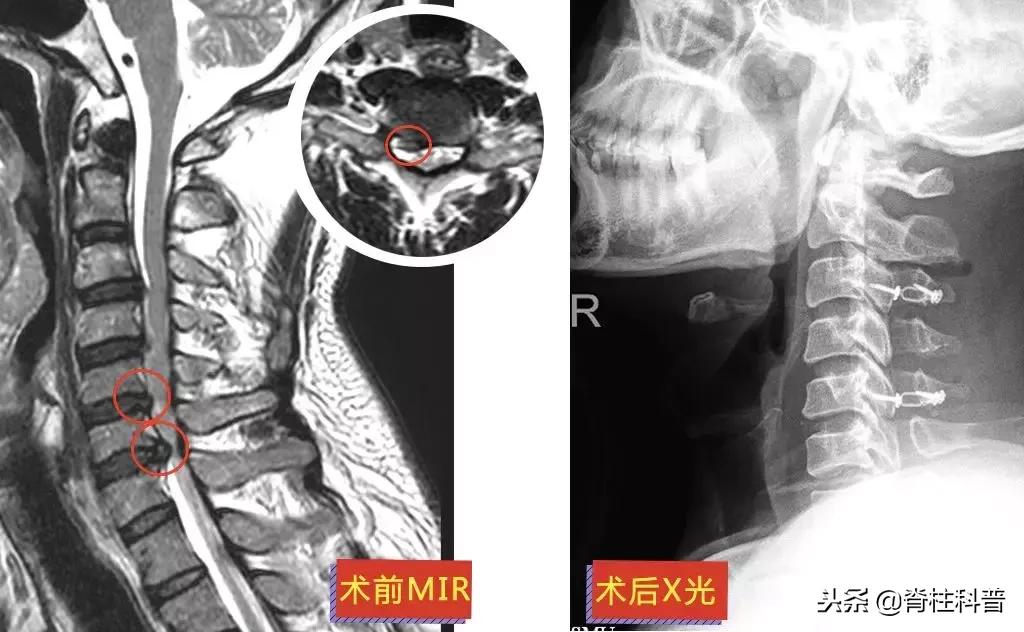

10天后,再次予以颈椎牵引治疗,症状稍缓解,可是颈痛发作频繁。经过熟人介绍,特意从茂名来到广州南方医科大学第三附属医院,找到张忠民主任医师治疗。在2018年9月20日在门诊被主任以“神经根型颈椎病”收治入院。10月3日手术,术后疼痛症状得到明显改善。

▲ 李三姨:术前MRI与术后X光